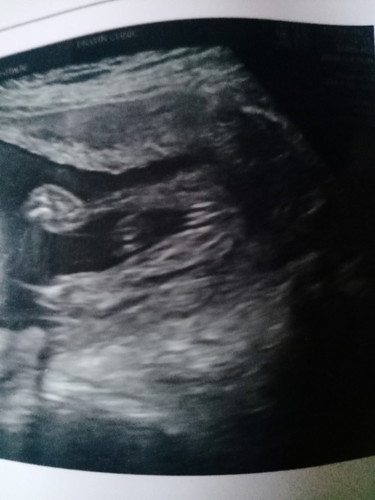

น้องเป็นผู้หญิงหรือผู้ชาย

ช่วยดูหน่อยค่ะว่าน้องเป็นผู้หญิงหรือผู้ชาย

น่าจะ ผญ นะคะ เหมือนกันลูกสาวบ้านนี้เลยค่ะ

ผู้หญิงค่ะแม่ เหมือนผลของเรา

ผู้หญิง98%ไปเลยค่ะแม่☺️

น่าจะผู้หญิงค่ะ

คิดว่าหญิงค่ะ

ผู้หญิงค่ะ

ลูกสาวคะ